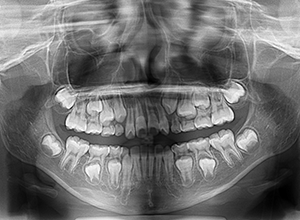

動的治療開始前(9歳7ヵ月)

動的治療開始前

(9歳7ヵ月)

口腔内所見 over jet -2.5mm、over bite 2.0mm、大臼歯関係はⅠ級 。Hellmanのdental ageはⅡCであり前歯部は反対咬合を呈していた。

セファロ所見 下顎骨体部は大きく下顎枝は前傾しており下顎角は鈍角であった。上顎骨はやや劣位で奥行きがなく下顔面高は高くなっていた。

パノラマ所見 上顎アーチレングスディスクレパンシー(-)であるが、その他の異常所見は認められなかった。